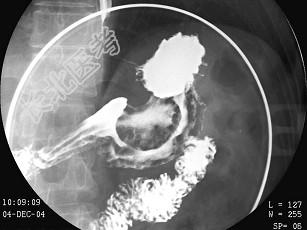

- 多项选择题男,55岁, 上腹饱胀不适2月,结合图像, 最可能的诊断是 ( )

E、胃癌